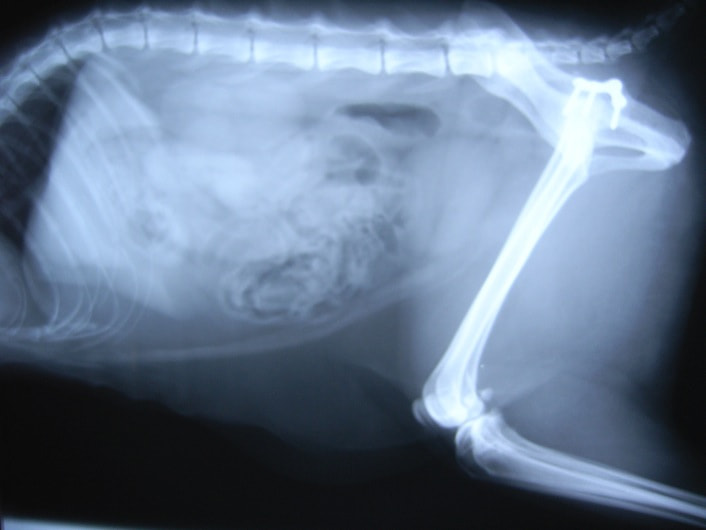

ペルシャ猫 11ヶ月齢 雄

他院にて左大腿骨遠位の成長板骨折(salter-harrisⅠ型)が認められており、治療相談を目的として来院。当院にて、キルシュナーワイヤーを用いたピンニングにより骨折部位の整復を行いました。術後の経過は良好で、現在も経過観察中です。

術前レントゲン